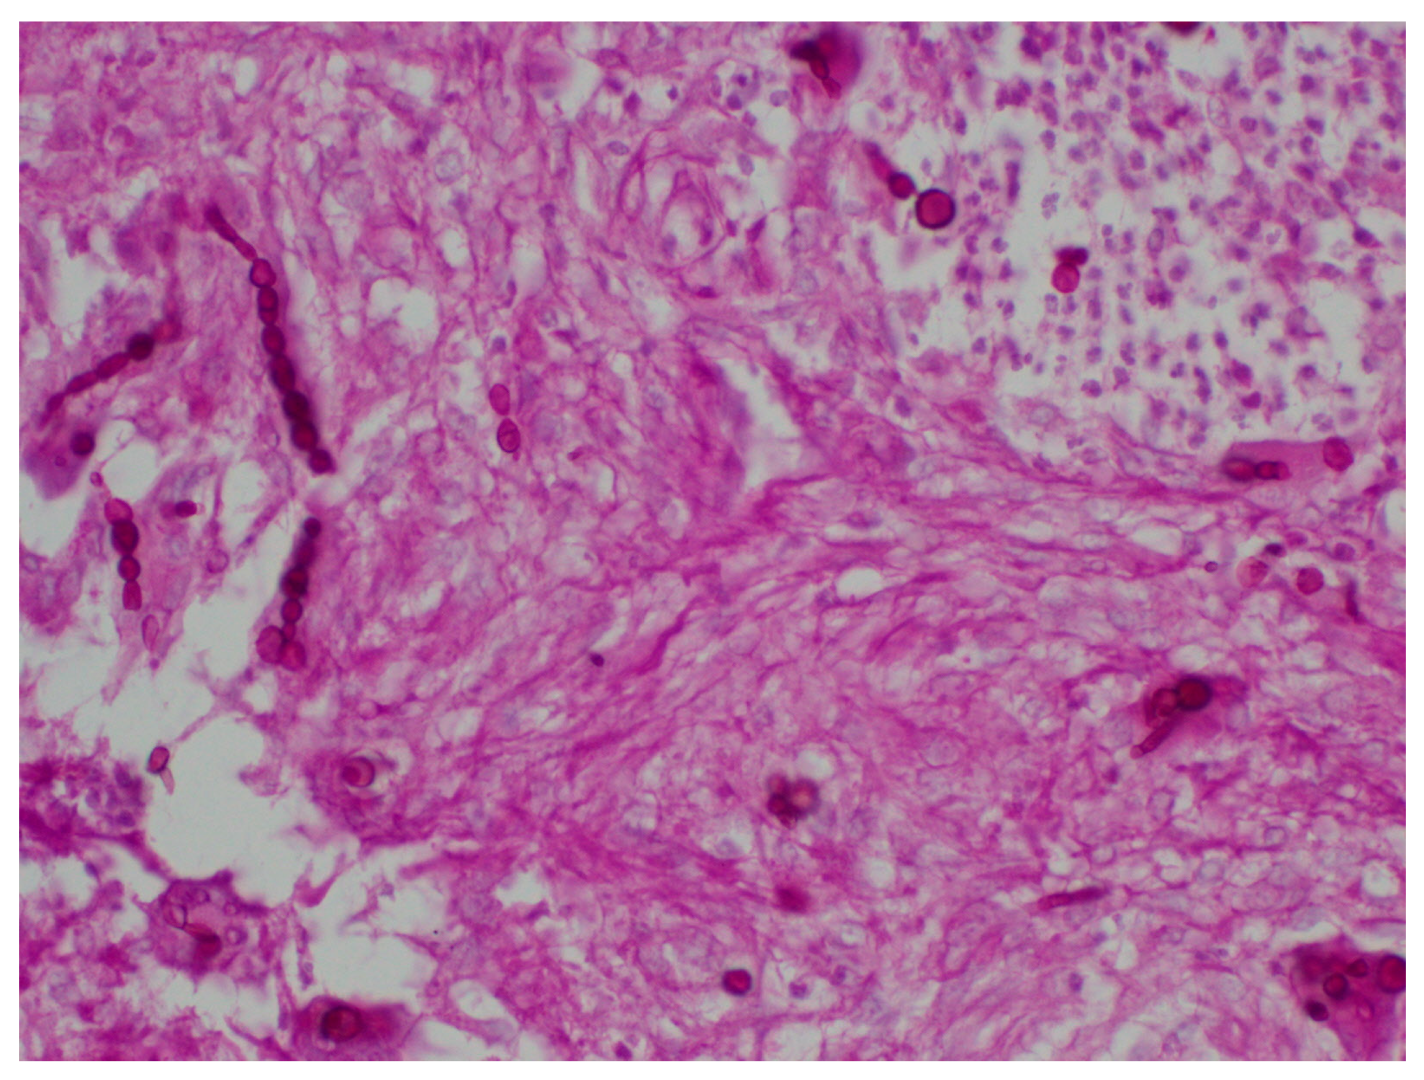

The special stains used to identify fungal structures are periodic acid-Schiff (PAS), Grocott Methenamine Silver stain (the polysaccharide of the fungal cell wall is detected by the reduction of Grocott’s alkaline hexamine-silver solution. It forms precipitates of silver ions turning black the cell wall of the fungi, which is known as the argentaffin reaction) and Fontana-Masson (used to identify dematiaceous fungi from hyaline hyphomycetes as it identifies argentaffin granules and melanin pigment) to observed filaments and yeasts [8] (Figure 4 and Figure 5).

Systemic involvement should be suspected when angioinvasion is observed through these special staining techniques, especially Methenamine Silver [5].

Figure 4. Rounded spores in phaeohyphomycosis (PAS 40×).

Figure 5. Filaments and chains of spores in phaeohyphomycosis (Gomori-Grocott 40×).